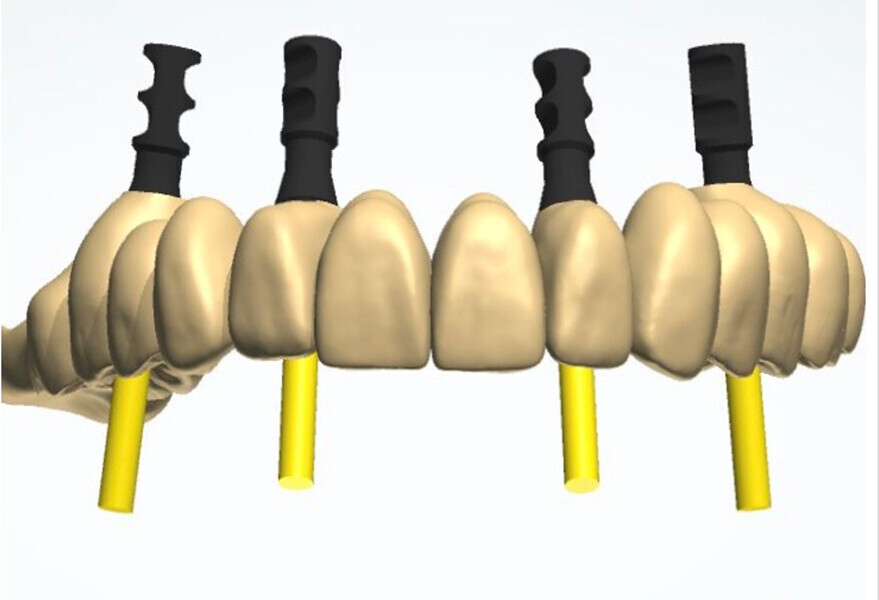

Compromised maxillary dentition treated with Straumann Pro Arch and a digital workflow